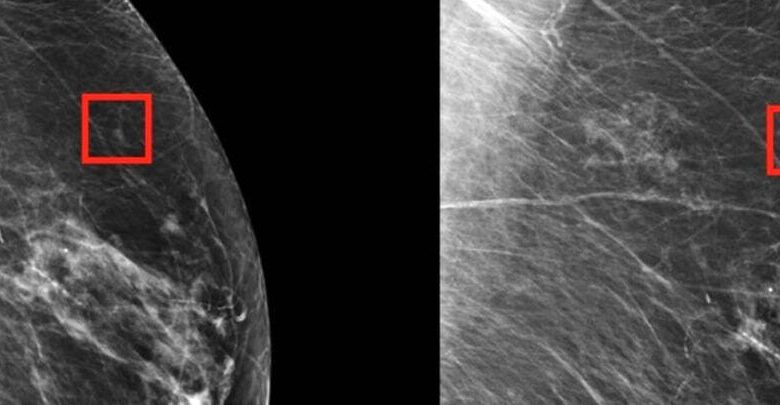

ماموگرافی استاندارد در تشخیص سرطان های کوچک سینه در زنان با الگوی سینه دارای چربی بالا (تراکم سینه) زیاد موثر است. سرطان سینه در ماموگرافی سفید و بافت چربی سیاه است. این کنتراست رنگی تشخیص سرطان های کوچک سینه را نسبتا آسان می کند. با این حال حالت مذکور در بانوان با سینه های متراکم برعکس است. بافت متراکم پستان در ماموگرافی سفید است که تشخیص سرطان های کوچک و سفید پستان را دشوارتر می سازد. به همین علت تشخیص سرطان سینه کوچک در یک سینه متراکم با چالش یافتن آدم برفی در طوفان برف قیاس شده است.

زنان جوان زیاد تر از زنان مسن سینه های متراکم دارند. یک مطالعه معتبر نشان داد که ۷۴ درصد از بانوان ۴۰-۴۹ ساله دارای سینه های متراکم می باشند. مطالعه مهم فرد دیگر که از طریق وب سایت کتابخانه ملی پزشکی آمریکا در اختیار علاقه مندان قرار گرفته است، نشان داده که ۹۸ درصد از سرطان های سینه در زنان با سینه های متراکم طی غربالگری ماموگرافی شناسایی نشدند. علاوه بر این، تراکم سینه یک عامل خطر قابل احتیاط برای ابتلا به سرطان سینه است و زنان با سینه های متراکم در معرض خطر بیشتری برای ابتلا به سرطان های تهاجمی پستان می باشند.